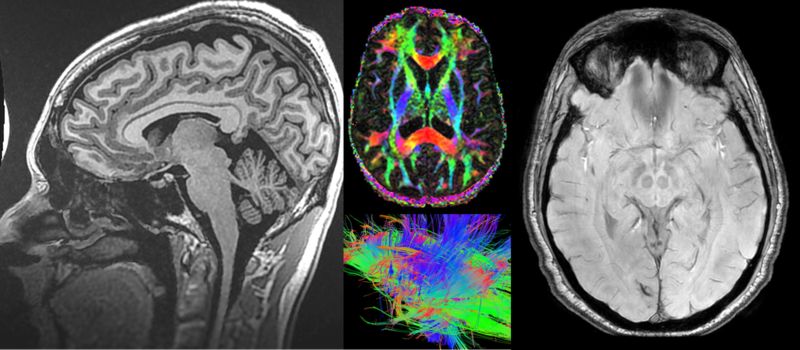

Study recruits troops to see how sleep deprivation affects the brain